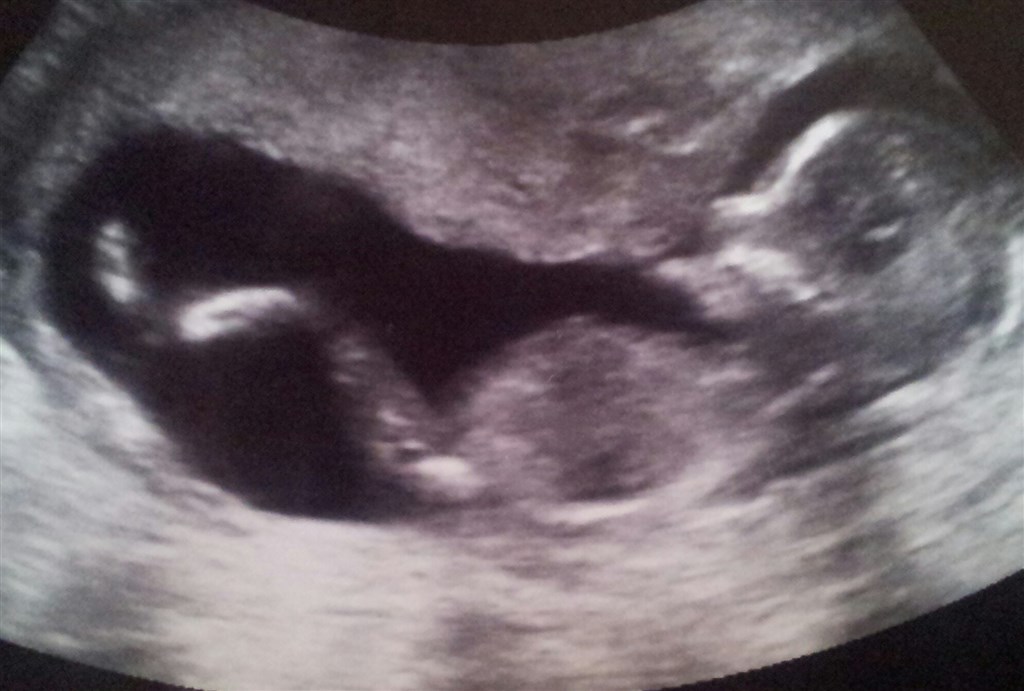

Så har vi været til Kønsscanning igår.

Babyen var meget hjælpsom med at vise kønnet. Men den havde navlestrengen mellem benene.

Men det lykkedes den meget dygtige scanningsdame at få nogle glimt af kønnet.

Vi venter os en lille pige